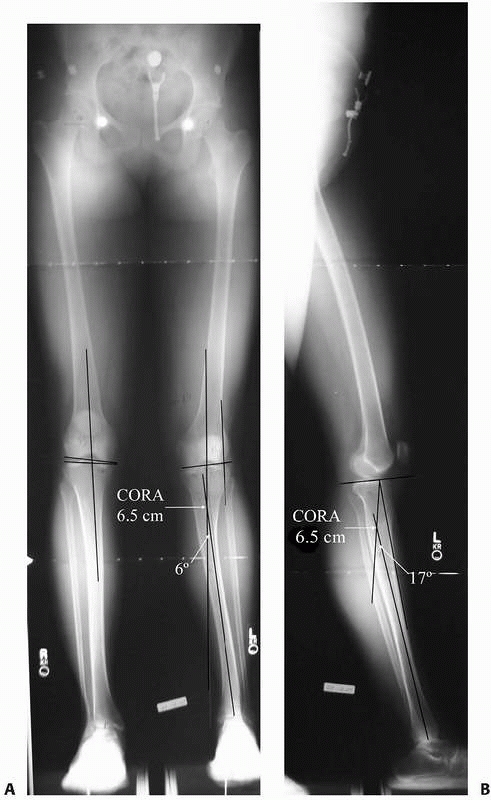

characterize; the angular deformity appears only on the AP or lateral

radiograph, respectively. If, however, the AP and lateral radiographs

both appear to have angulation with CORAs at the same level on both

views, the orientation of the angulation deformity is in an oblique

plane (Fig. 26-10). Characterization of the

magnitude and direction of oblique plane deformities can be computed

from the AP and lateral x-ray measures using either the trigonometric

or graphic method.18,37,72 Using the trigonometric method, the magnitude of an oblique plane angular deformity is

![]() |

FIGURE 26-10 A 28-year-old woman presented with complaints of her leg “going out” and her knee hyperextending. A.

51-inch AP alignment radiograph reveals a 6-degree apex medial deformity with the CORA 6.5 cm distal to the proximal tibial joint orientation line. B. The lateral alignment radiograph shows a 17-degree apex posterior angulation with a CORA 6.5 cm distal to the proximal tibial joint orientation line. This patient has an oblique plane angular deformity without translation. |